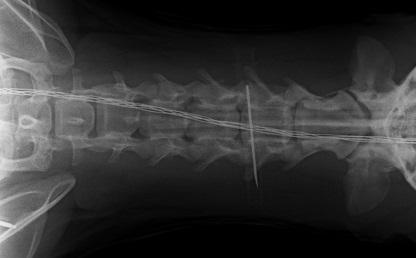

Op deze röntgenfoto ziet u de halswervels. De ruimte tussen de 4e en 5e halswervel en 5e en 6e halswervel waren vernauwd. Bij de rode pijl kunt u deze vernauwing het duidelijkst zien (dit is tussen de 5e en 6e halswervel) Zo'n vernauwing kan duiden op een nekhernia.

Op deze foto ziet u dat nog eens terug waarbij voor u het overzicht duidelijker is met de ribben en de luchtpijp(zwarte buis) onder de halswervels.

Vervolgens wordt er gecontroleerd of we op de juiste plek zitten door een pennetje langs de wervels te steken. Op een röntgenfoto zien we het pennetje en weten we 100% zeker dat we goed zitten. Daarna is er een stukje wervel weggefreesd van de 5e en 6e halswervel, zodat we zicht kregen op de tussenwervelschijf. Ook deze is gedeeltelijk weggefreesd tot aan het ruggemerg. Daarmee wordt de druk tegen het ruggemerg opgeheven. Tevens zit er altijd afwijkend weefsel (herniamateriaal) ter hoogte van de plek en dit wordt zoveel mogelijk verwijderd. Ook tussen de 4e en 5e halswervel is een openingetje gemaakt om de druk ter plaatste op te heffen.